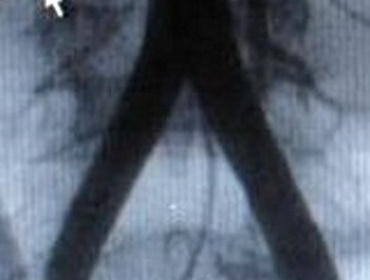

Popliteal pseudoaneurysm

1. Popliteal injury